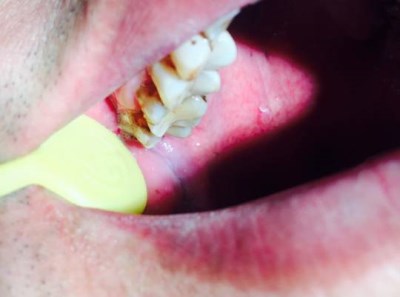

1).智齿冠周炎:由于智齿不能完全萌出在牙冠上方经常被牙龈覆盖,形成盲袋,不利于清洁,当机体下降,比如感冒,吃辛辣刺激食物,或者熬夜后就容易发生炎症。

2).邻牙损坏:智齿顶着前牙,导致前牙龋坏,严重的可能导致前牙无法保留。